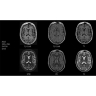

МРТ аппарат GE SIGNA Voyager 1.5T позволяет проводить полный спектр магнитно-резонансных исследований, включая нейровизуализацию, исследования опорно-двигательного аппарата, органов брюшной полости и малого таза, а также специализированные кардиологические программы.

• Неврология и нейрохирургия